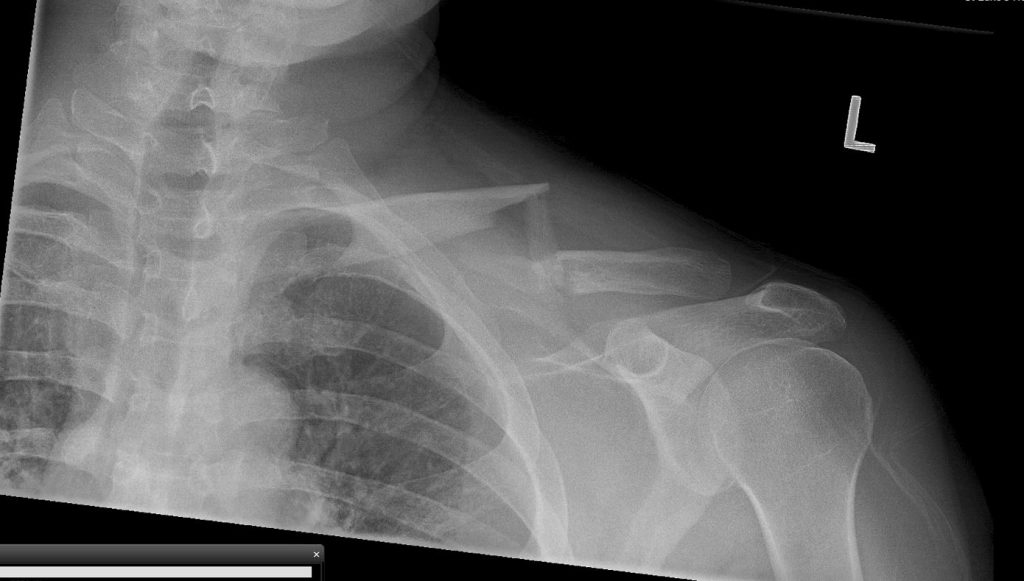

While skiing and enjoying a beautiful sunny day and the fresh snow, I fell and broke my left collarbone. Snow patrol brought me down from the slope and I was transported to an emergency room at a hospital in Pennsylvania.

After getting back to New York I scheduled a visit with Dr. Daniel Dziadosz at HSS. Dr. Dziadosz confirmed my worst fears, my collar bone was displaced and broken in multiple places. Dr. Dziadosz explained the nature of the injury and the steps involved in surgery and my rehabilitation. He made me feel comfortable and confident. I knew I was in the right place.